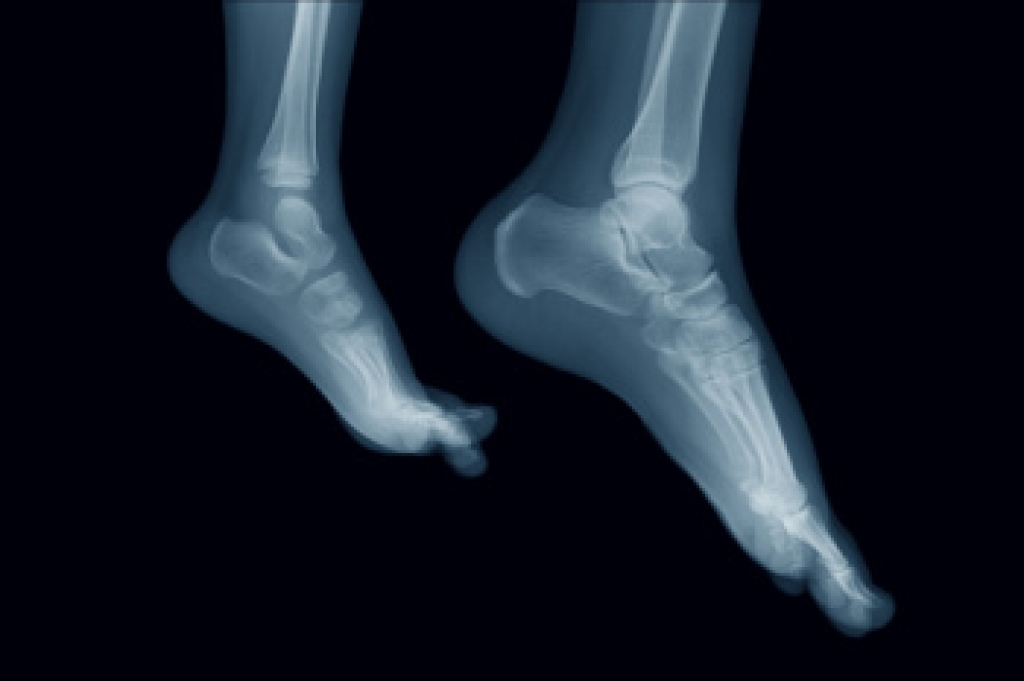

Preventing falls is an important part of protecting mobility and independence for older adults, and foot health plays a direct role in balance and stability. Painful feet, stiff ankles, weak calf muscles, reduced sensation from nerve damage, and deformities like bunions or curled toes can make walking less steady. Wearing safe footwear can help lower this risk by keeping the feet secure and improving contact with the ground. Shoes with a firm heel collar, a broad and slightly beveled heel, textured soles, and laces or straps can improve control during walking. Thin, firm midsoles may also help people better sense the surface beneath their feet. Shoes that are loose, worn down, backless, or higher than one inch at the heel can increase the chance of slipping. A podiatrist can examine the feet, identify problems affecting balance, and recommend appropriate care or footwear options. If you are concerned about falling, it is suggested that you make an appointment with a podiatrist for an exam and treatment.